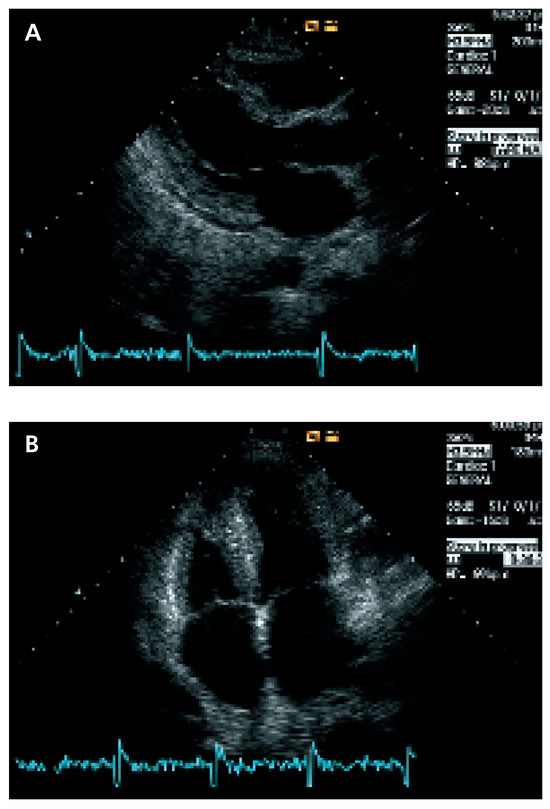

Update on Left Ventricular Hypertrophy

by Christina Attenhofer Jost

Detection and evaluation of left ventricular hypertrophy of unknown etiology by echocardiography is important in every cardiology practice. Causes of left ventricular hypertrophy include sarcomeric protein disorders (classical hypertrophic cardiomyopathy), metabolic disease (glycogen storage disease including LAMP2 deficiency, PRKAG2 mutations, Fabry disease), syndromic [...] Read more.

Detection and evaluation of left ventricular hypertrophy of unknown etiology by echocardiography is important in every cardiology practice. Causes of left ventricular hypertrophy include sarcomeric protein disorders (classical hypertrophic cardiomyopathy), metabolic disease (glycogen storage disease including LAMP2 deficiency, PRKAG2 mutations, Fabry disease), syndromic hypertrophic cardiomyopathy (Noonan’s syndrome, LEOPARD syndrome, etc.) and miscellaneous causes including systemic hypertension, amyloidosis, athlete’s heart and pheochromocytoma. Although there are several echocardiographic changes quite typical for some of the disorders, most changes are not 100% specific. ECG findings and symptoms provide important additional information. Genetic testing is increasingly important. Nowadays, a combination of ECG findings, symptoms, family history, genetic testing and findings of echocardiography provide the best means for differentiation of left ventricular hypertrophy. Full article

Figure 1